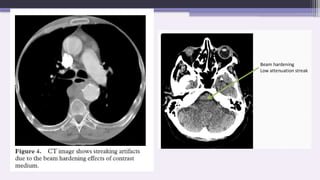

This type of artifact can occur both in

bony regions of the body and in scans

where a contrast medium has been used.

Dark and bright streaks radiating from

and between high-density objects, such

as dental amalgam.

Alternating dark and bright streaks in a

narrow band extending across the posterior

fossa